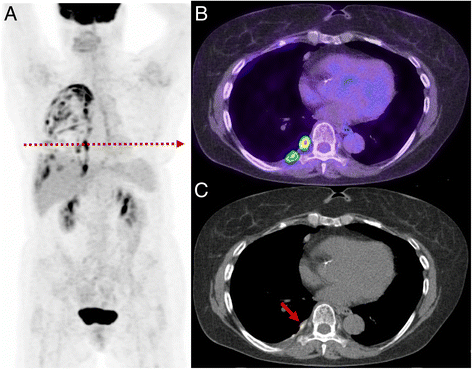

Fig. 6

Patient with prior lung malignancy presents for surveillance. The study demonstrates a typical appearance of inflammatory change post talc pleurodesis with intense multi-focal uptake evident throughout the pleural surface (a). On the axial PET/CT (b) and CT (c) the high focal uptake correlates with a site of talc on CT recognised by its high density. Such change can persistent for many years after pleurodesis